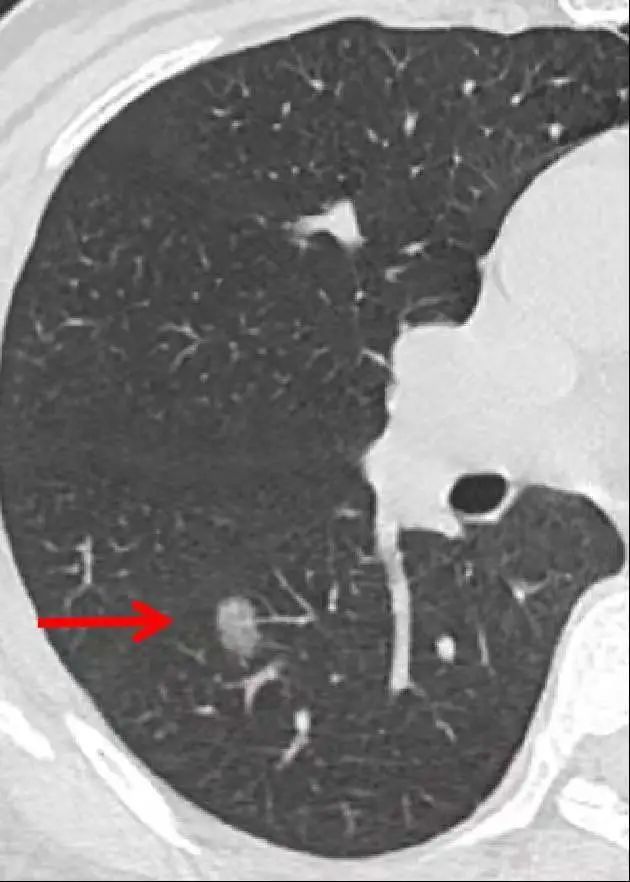

肺结节,在肺部影像表现为直径≤30mm的局灶性、类圆形、密度增高的实性或者亚实性肺部阴影,可为孤立性或多发性,不伴肺不张、肺门淋巴结肿大和胸腔积液。

根据肺结节大小不同:

? 直径<5mm称为微小结节;

?直径5mm-10mm称为肺小结节;

?直径11mm-30mm称为肺结节。

根据胸部CT判断是否存在磨玻璃密度成分,可将肺结节分为:纯磨玻璃结节(PGGN)、实性结节和部分实性结节(PSN)